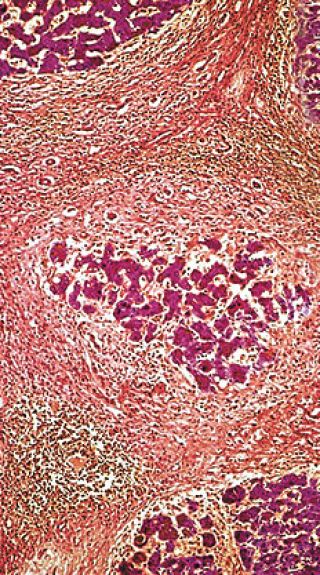

Micrografía de la sección tranversal de un fino tejido del hígado que muestra el estado avanzado de la cirrosis, un estadio en que el hígado responde a la lesión o muerte de algunas de sus células produciendo filamentos que entrelazan (rojo amarronado) los lóbulos activos del hígado (rosado). El hígado es un órgano que metaboliza productos químicos, almacenando algunos y excretando otros. La cirrosis es a menudo una respuesta al daño causado por el consumo excesivo del alcohol.